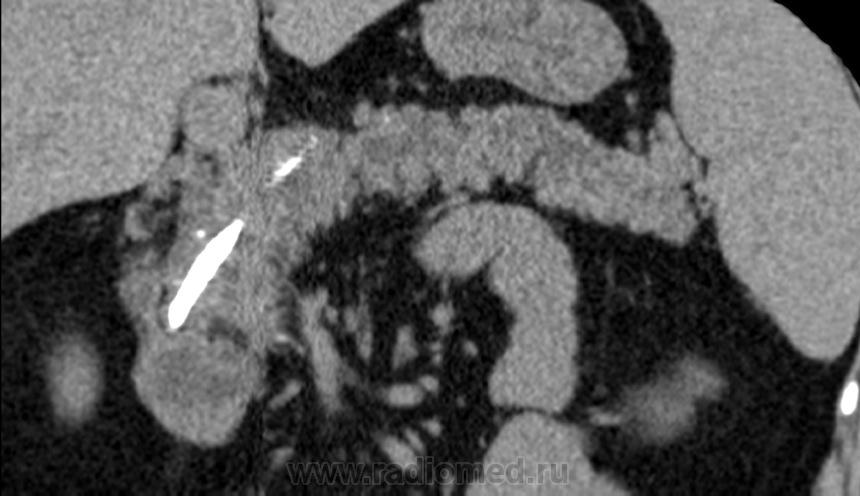

Итак пациент мужчина 34 года, в анамнезе - 16 эпизодов острого панкреатита (!). Пациенту была выполнена ЭРХПГ которая выявила наличие двух стриктур протока Вирсунга в области головки поджелудочной железы (доброкачественная стриктура Вирсунгова протока). На представленных мной изображениях определяется неоднородная структура поджелудочной железы с гиподенсными участками в области тела/хвоста и наличием паренхиматозных кальцификатов (b & c). Такая картина указывает на хронический панкреатит. В области головки визуализируется стент (a), установленный в Вирсунгов проток, с свободным концом в просвете 12-ти перстной кишки. Такое стояние стента является правильным. На данный момент, единственной адекватной терапией при доброкачественных стриктурах протока поджелудочной железы (и при некоторых опухолях исходящим из протока или обтурирующих его, когда невозможно выполнить резекцию) является эндоскопическое стентирование протока, что обеспечивает нормальный отток секрета поджелудочной в кишечник.